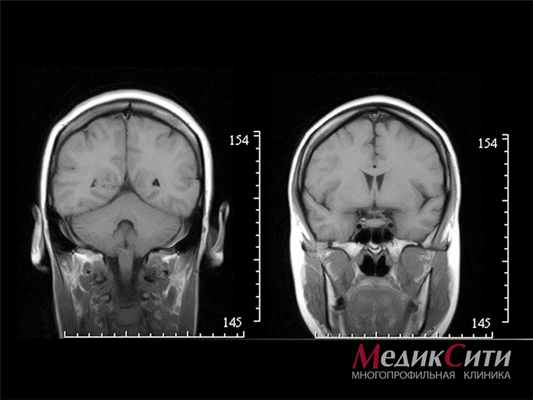

МРТ головного мозга

Для диагностики всех видов черепно-мозговых травм самыми информативными являются рентген и магнитно-резонансная томография. Это позволяют исключить перелом костей черепа.